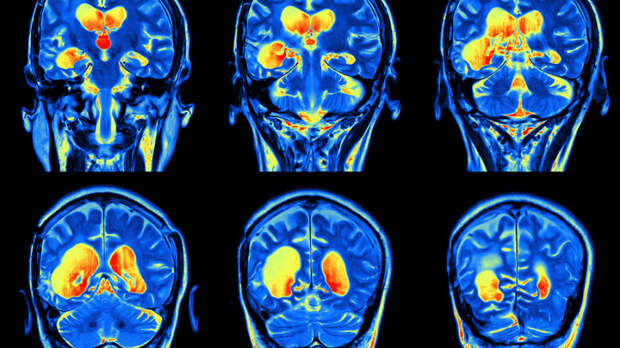

Исследователи пришли к выводу, что депрессия вызывает заметные изменения в орбитофронтальной коре головного мозга. Результат основан на проведенном в Китае МРТ-сканировании опытной группы из 909 людей. 421 человеку из них был поставлен диагноз депрессия, в то время как вторая половина, состоящая из здоровых людей, позволяла определить степень отклонения от нормы.